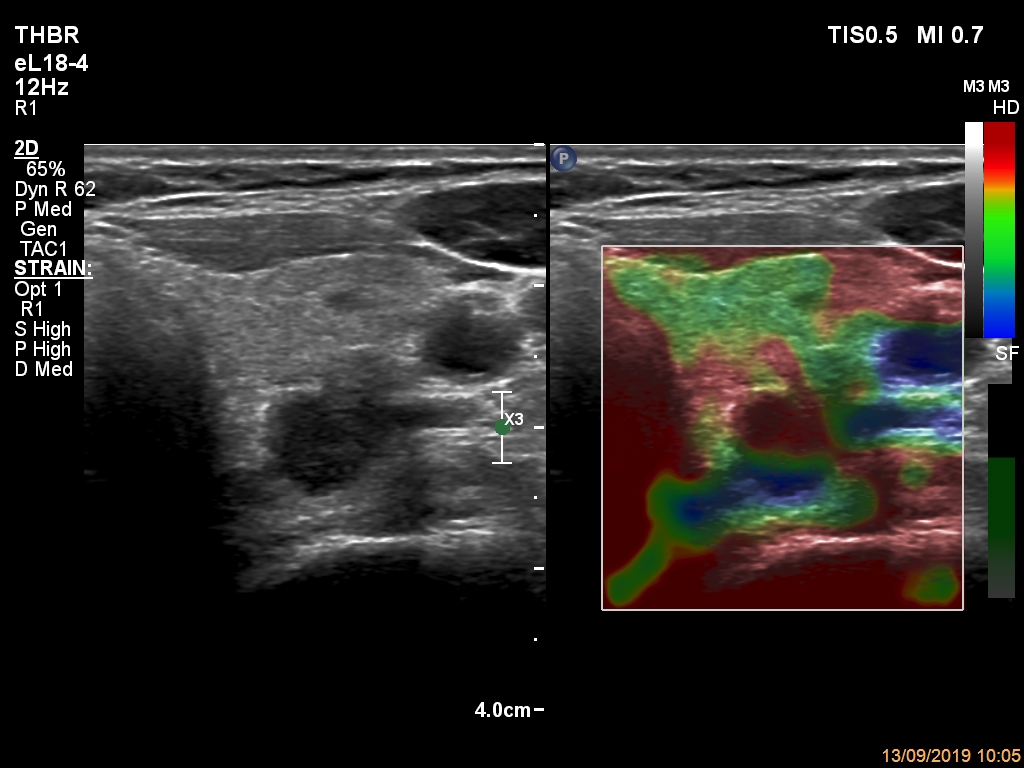

The borders of the nodule - case 2089 (ultrasonographic picture 10)

Right lobe, longitudinal scan

Left lobe, trasnverse scan. The lesion proved to be hard on elastography.